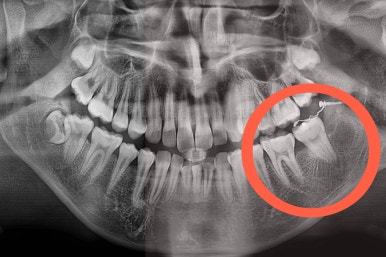

구멍이 뻥 뚫린게 보이실 거에요.

매복 사랑니를 발치한 자리인데요.

사랑니를 발치하며 앞쪽에 살려 써야하는 어금니에 작은 장치를 부착했어요.

어금니를 당겨줄 미니스크류도 사랑니를 발치하면서 식립해 주었어요.

사랑니 뽑은 자리가 매우 커 보이는데요.

보통은 3~6개월 지나면 뼈가 차오른답니다.

매복 치아였기 때문에 입 안에서는 장치도 거의 보이질 않죠.

해당 장치와 미니스크류 사이에 교정용 고무줄을 연결하여 지속적으로 당겨줍니다.